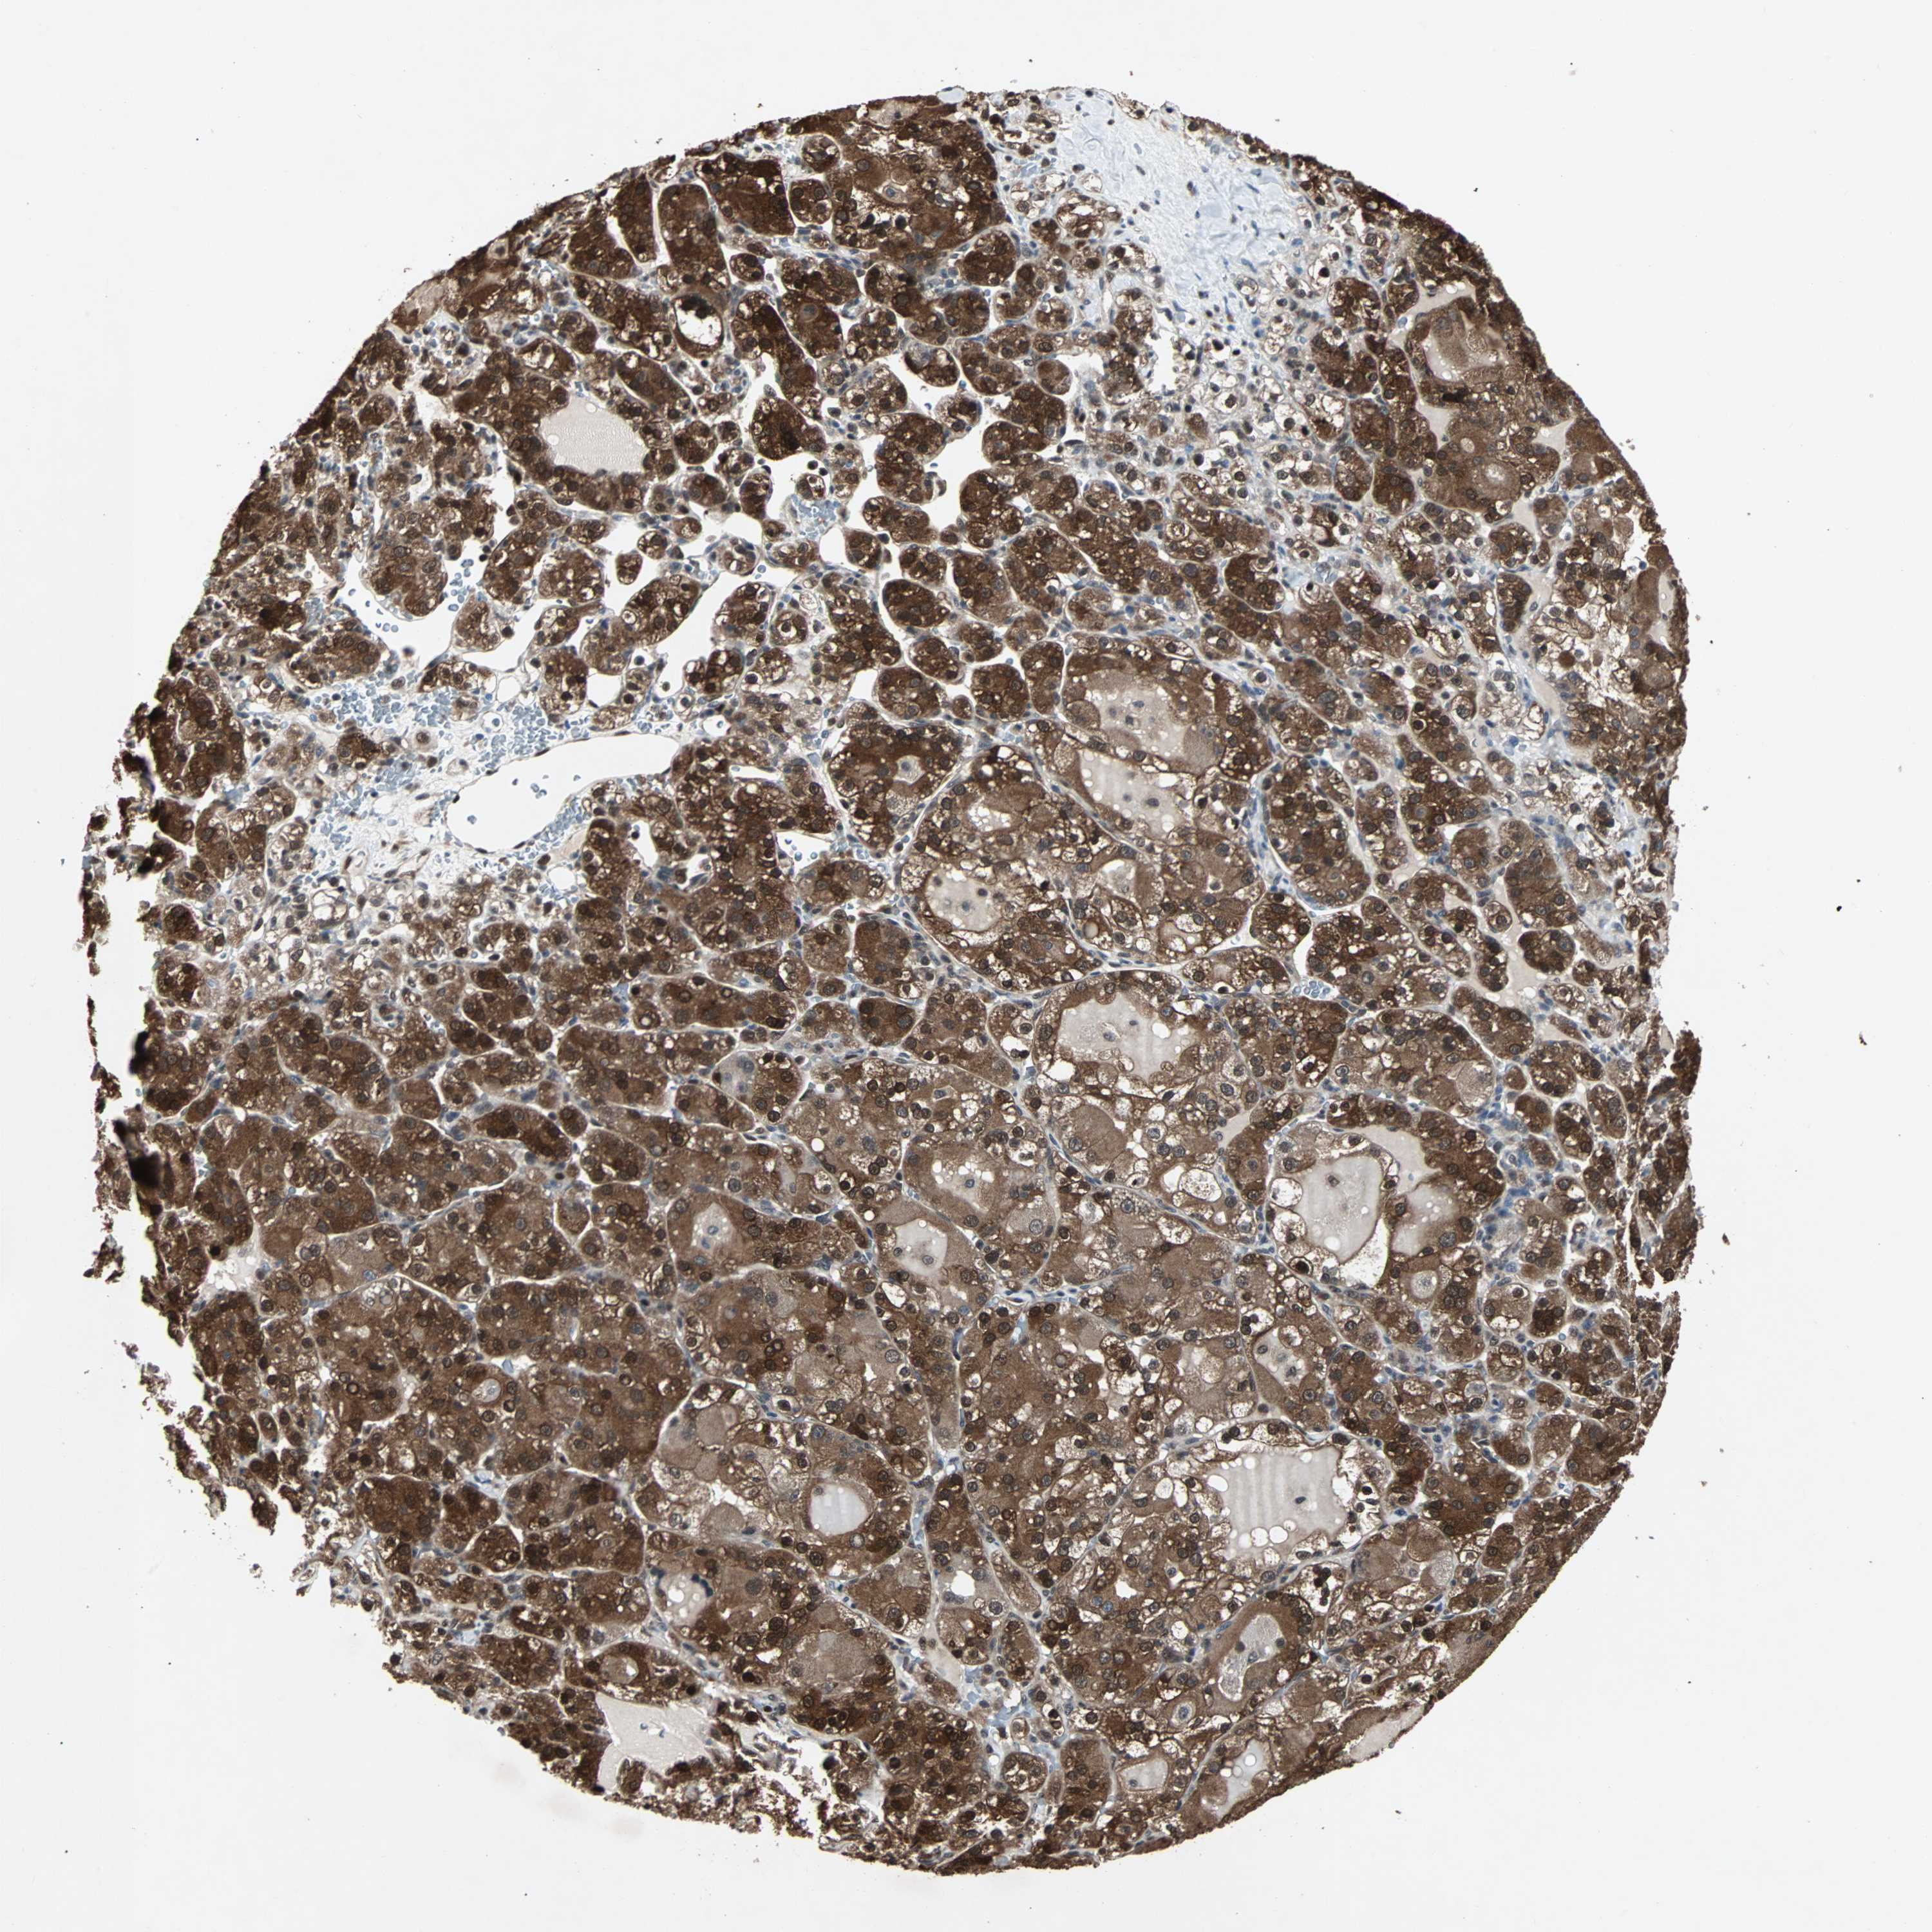

KIDNEY RENAL CLEAR CELL CARCINOMA (TCGA) - Interactive survival scatter ploti

The Survival Scatter plot shows the clinical status (i.e. dead or alive) for all individuals in the patient cohort, based on the same data that underlies the corresponding Kaplan-Meier plots. Patients that are alive at last time for follow-up are shown in blue and patients who have died during the study are shown in red.

The x-axis shows the expression levels (FPKM) of the investigated gene in the tumor tissue at the time of diagnosis. The y-axis shows the follow-up time after diagnosis (years). Both axes are complimented with kernel density curves demonstrating the data density over the axes. The top density plot shows the expression levels (FPKM) distribution among dead (red) and alive patients (blue). The right density plot shows the data density of the survived years of dead patients with high and low expression levels respectively, stratified using the cutoff indicated by the vertical dashed line through the Survival Scatter plot. This cutoff is automatically defined based on the FPKM cutoff that minimizes the p-score. The cutoff can be changed by dragging the vertical line or by entering a cutoff value in the square labeled "Current cut-off".

Under the Survival Scatter plot the p-score landscape (black curve; left axis) is shown together with dead median separation (red curve; right axis). Dead median separation is the difference in median mRNA expression between patients who have died with high and low expression, respectively. It is calculated as follows: median FPKM expression of dead patients with high expression - median FPKM expression of dead patients with low expression. This is intended to aid the user in visually exploring custom cutoffs and the associated p-scores and dead median separation.

Individual patient data is displayed and can be filtered by clicking on one or more of the category buttons on the top of the page. Categories describing expression level and patient information include: high, low, alive, dead, female, male and tumor stages. The scale of the x-axis can be toggled between linear and log-scale by clicking on the "x log" button. Mouse-over function shows TCGA ID, patient information and mRNA expression (FPKM) for each patient.

& Survival analysisi

Kaplan-Meier plots summarize results from analysis of correlation between mRNA expression level and patient survival. Patients were divided based on level of expression into one of the two groups "low" (under cut off) or "high" (over cut off). X-axis shows time for survival (years) and y-axis shows the probability of survival, where 1.0 corresponds to 100 percent.

ACLY is potential prognostic, high expression is favorable in Kidney Renal Clear Cell Carcinoma (TCGA)

Best expression cut offi

Based on the FPKM value of each gene, patients were classified into two groups and association between prognosis (survival) and gene expression (FPKM) was examined. The best expression cut-off refers the FPKM value that yields maximal difference with regard to survival between the two groups at the lowest log-rank P-value. Best expression cut-off was selected based on survival analysis .

When clicking on this number, the vertical dashed line indicating cut-off, the interactive survival plot, and the Kaplan-Meier curve will be adjusted to show results based on the best expression cut-off.

: 197.59

Median expressioni

Median expression refers to the median FPKM value calculated based on the gene expression (FPKM) data from all patients in this dataset. When clicking on this number, the vertical dashed line indicating cut-off, the interactive survival plot, and the Kaplan-Meier curve will be adjusted to show results based on the median expression.

: N/A

TCGA RNA samplesi

RNA-seq data is reported as average FPKM (number Fragments Per Kilobase of exon per Million reads), generated by the The Cancer Genome Atlas (TCGA) .

Normal distribution across the dataset is visualized with box plots, shown as median and 25th and 75th percentiles. Points are displayed as outliers if they are above or below 1.5 times the interquartile range. FPKM values of the individual samples are presented next to the box plot.

Average pTPM 159.7

Number of samples 521